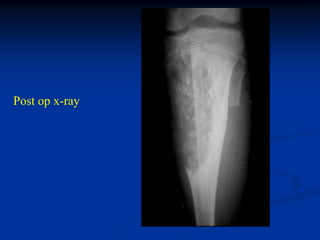

Post op x-ray

tumor cavity filled

with radiolucent

cement